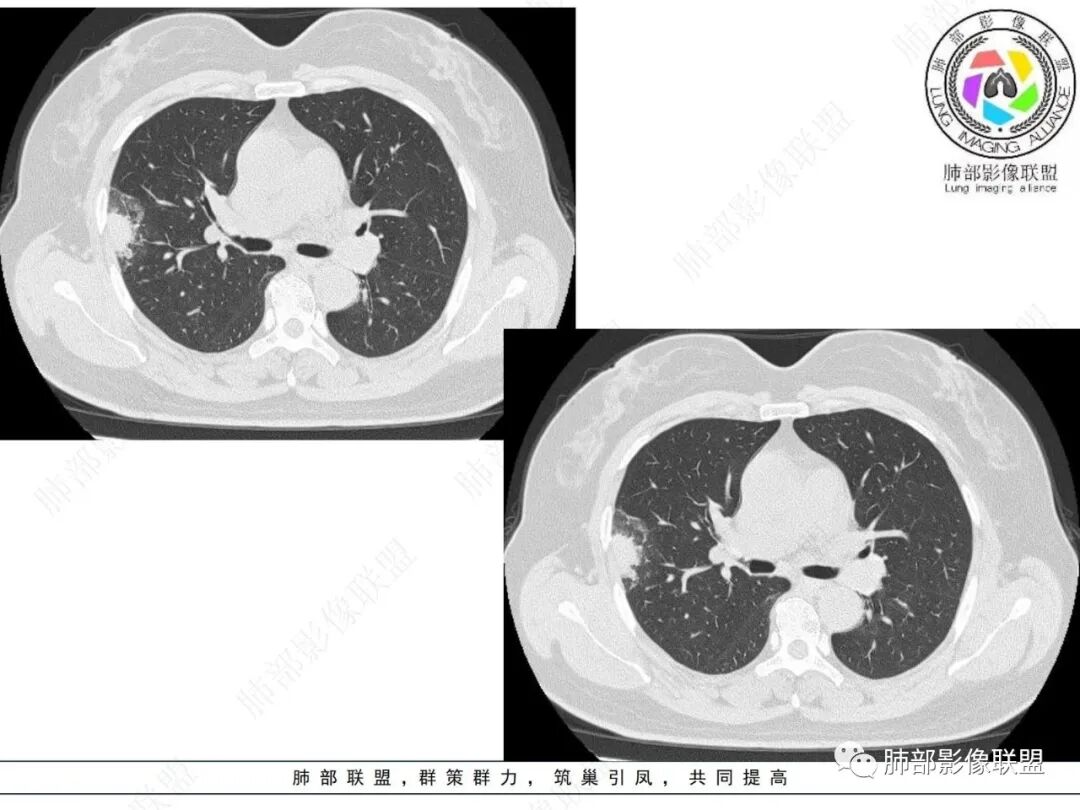

右肺上叶胸膜下混合磨玻璃团片影。

周围磨玻璃部分间杂条索状高密度区,密度欠均匀(可疑重力分布趋势),其磨玻璃影边界大多较清楚或可分辨,部分“L型”边缘,提示小叶间隔阻挡可能。血管穿行自如,可疑远端支气管进入。

未见卫星病灶,远处未见磨玻璃结节影。

双肺门及纵隔未见明显增大淋巴结。心包及胸腔未见积液。

右肺上叶胸膜下混合磨玻璃结节,磨玻璃部分与实性部分密度都不均匀,病灶有重力分布效应,小叶间隔阻挡,收缩力羸弱。中老年女性,如此大范围病灶,缺乏临床表现,会让人警惕非感染性病变,尤其是恶性病灶可能!

其他需要鉴别的原有病灶伴出血,炎性病灶等等,感染性病变需要排除的尚有隐球菌,临床表现逍遥,病灶未出胸膜下,周围磨玻璃等等……

经验性抗炎治疗,病灶活检是较好的鉴别方式。单就影像而言,复查病灶进行性进展,沿支气管出现播散灶也是粘液腺癌诊断的有力证据。